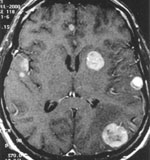

A Magyar Neuro-Onkológiai Társaság főtitkára szerint nem igazak azok a hírek, hogy agydaganatot megelőző elleni vakcinát hoz forgalomba Svájcban egy amerikai cég. Fedorcsák Imre a Népszabadságnak azt mondta: elég megnézi a gyártó honlapját, hogy kiderüljö

Az amerikai laboratórium hétfőn jelentette be, hogy felhatalmazást adott az agytumor elleni első vakcina forgalomba hozására Svájcban. A DCVax-Brain nevű oltóanyag a tervek szerint 2009-től lenne elérhető az Egyesült Államokban és Európa más országaiban.

Fedorcsák Imre szerint szó sincs megelőző oltóanyagról, ahogy az esetleges gyógyító eljárás forgalmazásáról sem. Az eljárás kísérleti stádiumban van, a kezelések egyelőre a túlélés esélyeit növelik.